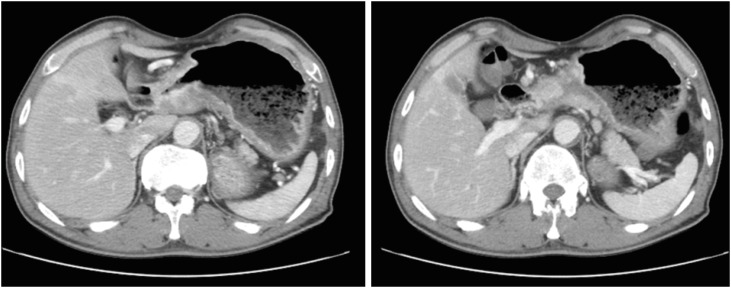

A 57-year-old man was informed regarding a possible diagnosis of gastric cancer at a local clinic on November 15, 2016, based on the results of endoscopic examination previously performed following his complaints of weight loss, abdominal pain, and indigestion. On the same day, the patient visited the department of gastroenterology at a university hospital for endoscopy including biopsy. The tests revealed advanced gastric cancer in the distal antrum (Fig. 1). Abdominal computed tomography (CT) scans subsequently confirmed the presence of cancer and metastasis. The results showed invasion of the entire wall of the antrum with regional lymph node metastasis (Fig. 2). He was diagnosed with stage IIIB gastric cancer (T4N2M0). On December 6, 2016, the patient underwent subtotal gastrectomy with Billroth I anastomosis and cholecystectomy, and was started on chemotherapy. Despite the treatment, he died of gastric cancer on January 9, 2018. Apart from having received treatment for chronic hepatitis B, the patient had never been diagnosed with any disease of the GI tract prior to the gastric cancer diagnosis. During the endoscopy performed on November 15, 2016, he was not tested for H. pylori infection; in addition, he never underwent any tests for H. pylori infection. We were thus unable to determine the presence of H. pylori infection. He had a 1–10 pack-years history of smoking, did not drink, and had no particular relevant family medical history. At the time of his job history survey, the patient was working as a day laborer; his official job history could not therefore be established. We accordingly reviewed his employment insurance records, the National Tax Service (NTS) reports, and his own statements. Based on the combined information, we summarized that the patient had worked as an oxygen cutter at shipbreaking workplaces from 1978 to the 1990s (for approximately 17 years). Furthermore, during the 1990s and 2010s (until 2016), he worked for 7 years at building demolition workplaces as a member of the boiler dismantling crew, and also spent another 14 years in dismantling factories and various thermal power generation plants. Altogether, the patient had presumably worked for about 40 years since 1978 as an oxygen cutter at workplaces that dismantle ships, buildings, boilers, and thermal power plants.

Fig. 1

Patient A: endoscopic findings. Endoscopy showing advanced gastric cancer with distal antrum and near gastric outlet obstruction.